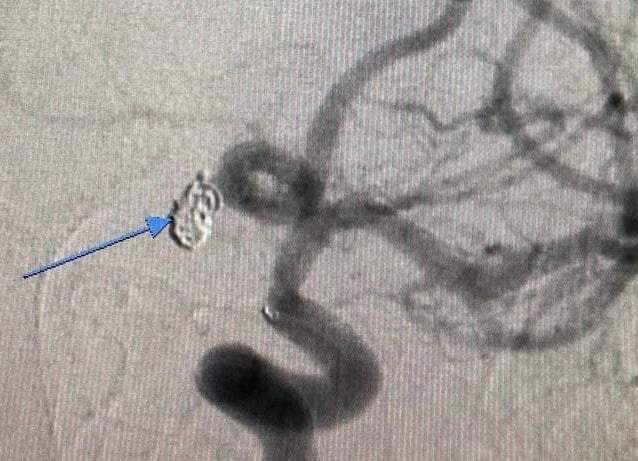

Врачи сразу провели компьютерное исследование ангиографии. Это помогло заметить кровь в головном мозге. Они поняли, что это привело к тяжелому состоянию.

В эндоваскулярном центре провели консилиум врачей и решили, что нужно провести эмболизацию аневризмы. Медикам пришлось ввести специальный проводник через доступ к лучевой артерии в сосуды головного мозга.